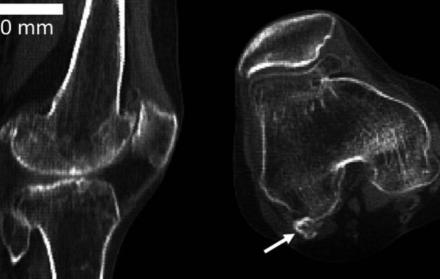

Las flechas indican la posición de fabela en las articulaciones actuales.

La fabela es un hueso sesamoide, es decir, un hueso redondeado, que crece en el tendón de un músculo (el mayor es la patela, o rótula). Por su tamaño y por lo poco común de su presencia, a veces en las radiografías se lo confunde con un fragmento óseo o un cuerpo extraño.